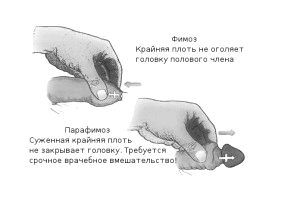

- фимозом,

При набряку і почервоніння голівки, появі хворобливих виразок на ній і крайньої плоті, загальної слабкості та високої температури діагностують гангренозну форму баланопостіта і розвиток фімозу.

- звужується уретра і розвивається фімоз,